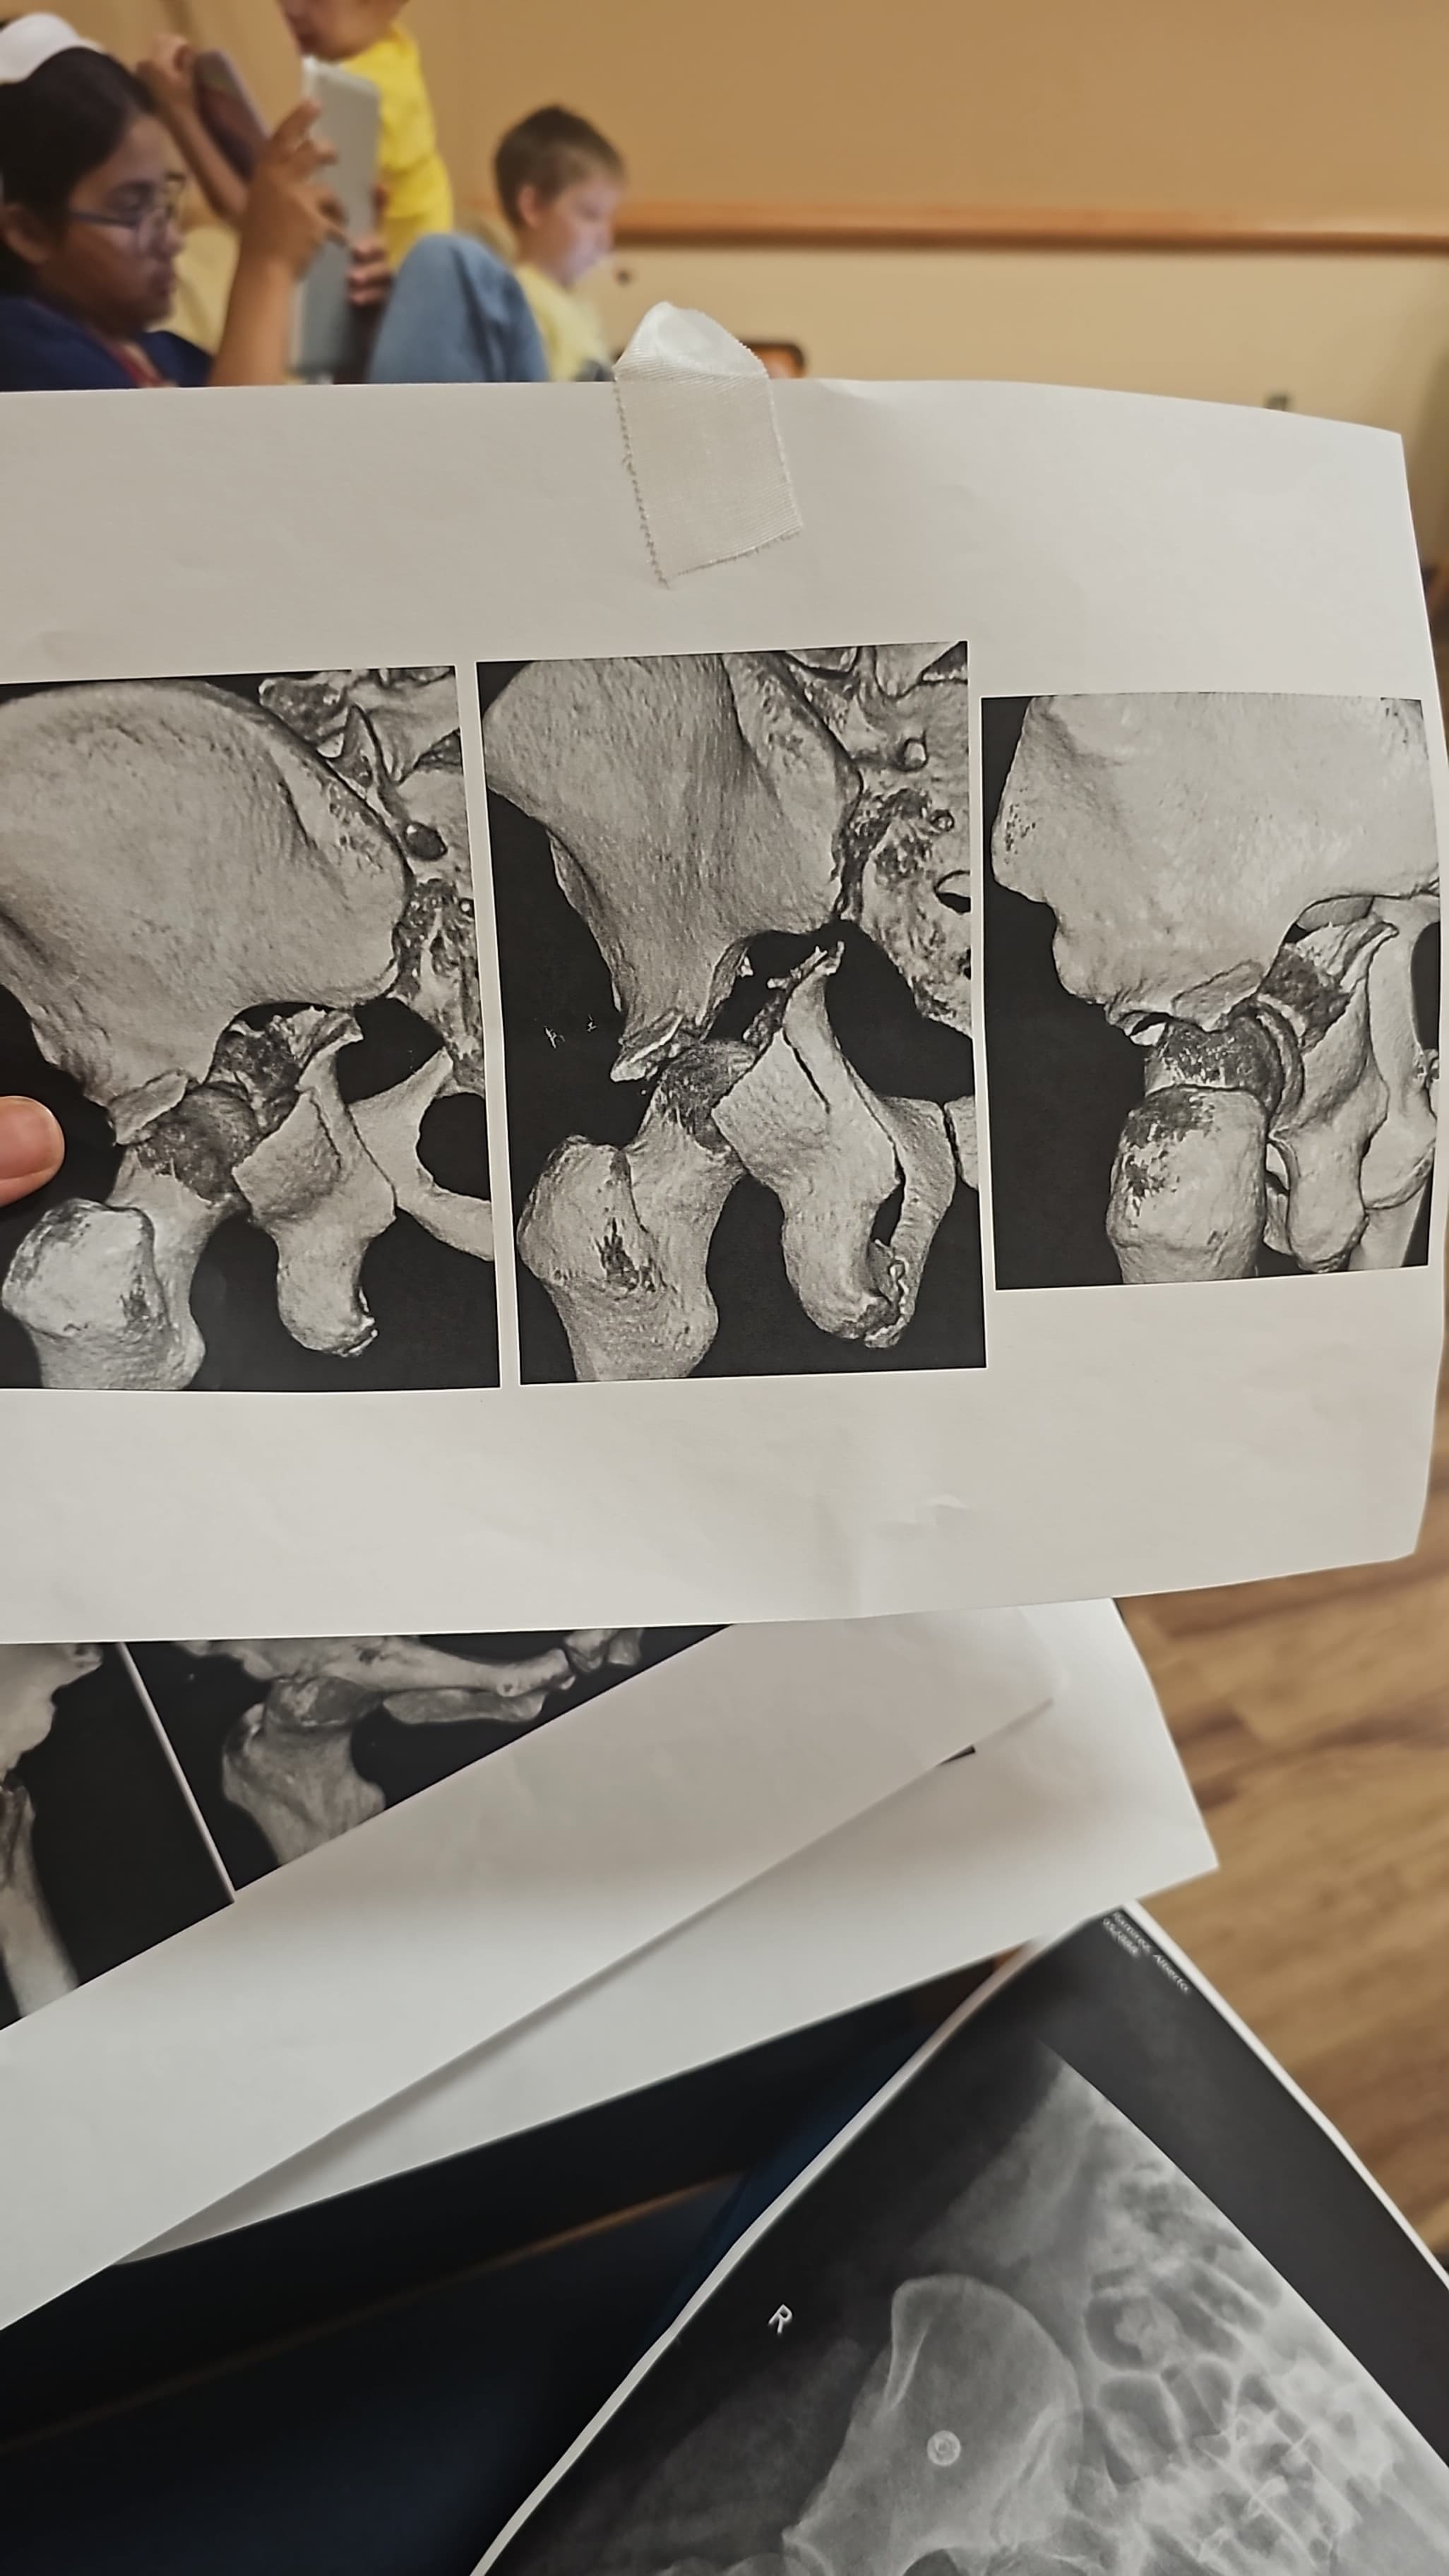

Alberto, my cousin and a beloved member of our family, was recently involved in a serious car accident caused by a drunk driver. The crash left him with a broken arm and a broken hip and severe damage nerve, and he has already undergone two surgeries. Right now, he is just beginning his long recovery journey is going to take him a while to walk and were gonna have to teach him how to walk all over again, and our family is doing everything we can to support him.

Alberto will need several months of physical therapy and specialized care at a rehabilitation hospital to regain his strength and mobility. The costs of medical treatment, therapy, and ongoing care are adding up quickly, and we want to make sure he has everything he needs for the best possible recovery. He lives with us and is a cherished part of our household. This accident has deeply affected all of us, and we are determined to help him get back on his feet.